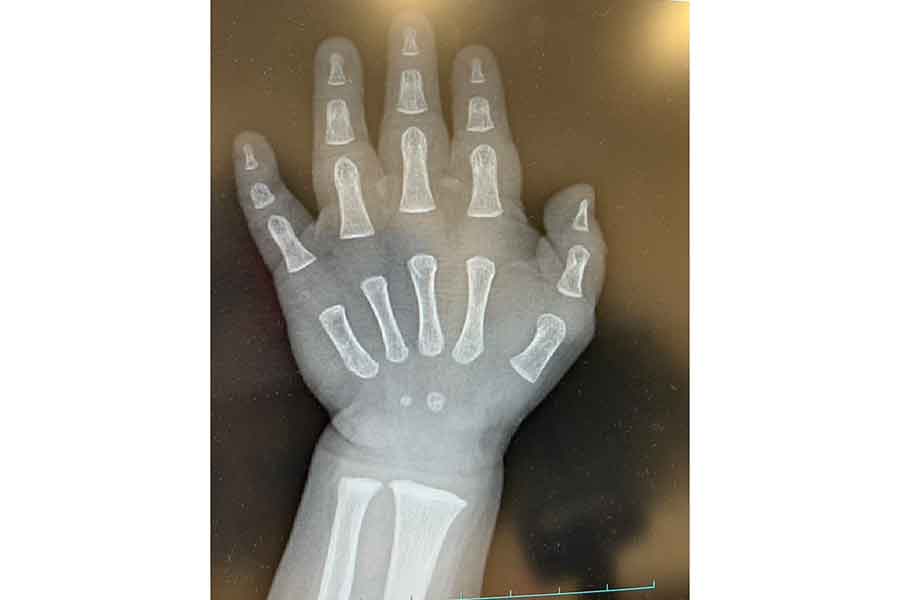

そんなコメントとともに投稿されたのは、1枚のレントゲン写真です。手首から指先までの小さな手は、X線撮影でもわかるほどぷっくり。成長段階の骨はまだ小さく、間隔が離れています。

無機質なレントゲン写真からも伝わる愛らしさは反響を呼び、2.7万件もの“いいね”が集まりました。リプライ(返信)には、「かわいい。もーこんなんだけ見てたい」「芯……からかわいいってことでは?」「小さくても体の構造がしっかり備わってて、生命の力強さを感じます。骨もかわいいんですねっ」「むちむちクリームパンも相まってかわいすぎる~!」などの声が殺到。

さらに、「ちなみに手の付け根の骨(手根骨)は、子どもが大きくなるにつれて数が増えたり形が成熟したりしていきます。つまり……とにかくかわいい ちなみに手だけじゃなく全身かわいいぞ!」といった整形外科医や、「子どもってレントゲンでも、かわいさが写っちゃいますよね」という小児科医からの声も上がっています。